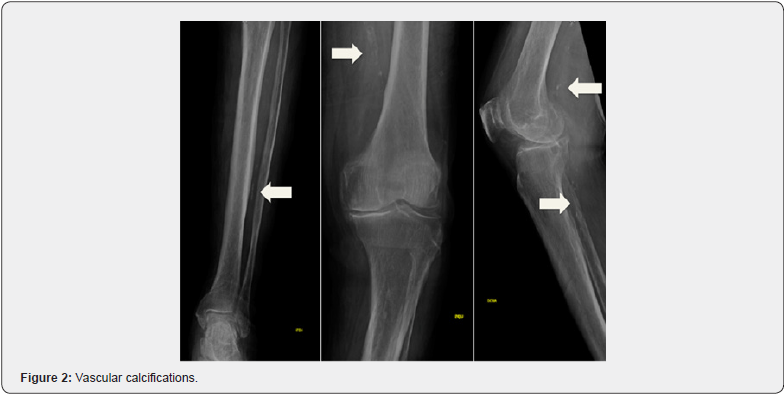

A 73-year-old male patient presented our institution with painful and extensive leg ulcers that had progressed over 2 months. He was diagnosed with metastatic non-small cell lung cancer on treatment with atezolizumab for 4 years without evidence of progression disease and castration resistant prostate cancer with bone lesions, a condition for which he was receiving androgen deprivation therapy and enzalutamide for 2 years. Additional past medical history included hypertension and type 2 diabetes mellitus on treatment with amlodipine and sitagliptin respectively. Dermatological examination found large retiform leg ulcers with a necrotic background and superinfection signs, surrounded by a purplish rim on his lower limbs (Figure 1). The lesions were extremely painful to palpation. Swabs taken from the ulcers revealed infection with Pseudomonas aeruginosa and Staphylococcus aureus highly sensitive to fluoroquinolones. Leg X-rays showed several arterial calcification (Figure 2) and skin biopsy revealed calcification in muscular arteries with vascular necrosis, compatible con calciphylaxis diagnosis (Figure 3).